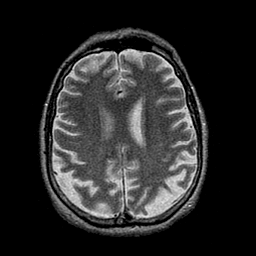

Alzheimer's disease: overlay -- Slice #34

[Home][Help][Clinical] Slice 34